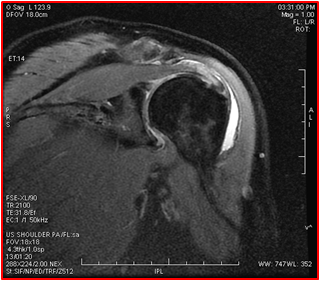

肩关节有很多的肌腱和肌肉,可以做很多大范围的动作,同时也最容易产生疾病。肩关节及其周围的肌肉筋骨疼痛被称为肩痛。中老年人常有肩部疼痛的困扰,举臂梳头、脱上衣、沐浴等都会有困难,甚至睡觉翻身都会因为肩痛而惊醒。肩周炎又称肩关节周围炎,俗称凝肩、五十肩。由于“肩周炎”这个概念在很多人的思想里已经根深蒂固,所以绝大部分人都认为“肩痛就是肩周炎”、“忍忍就过去了”,有些人不到医院,而是自行按摩推拿、“爬墙”锻炼,这样的医疗常识误区导致很多患者病情加剧,并且顽固地认为“肩周炎就是治疗不好的”。那么,肩痛的原因就是肩周炎吗?有研究数据表明,真正的肩周炎发病率很低,只占肩痛患者的10%-15%,导致肩痛的最常见原因是肩袖损伤,其中60岁以上由于肩痛就诊的老年人中,肩袖损伤的比例超过60%。 我们来看以下两个病例 病例1:苏某,男性,66岁。平时肩部偶有不适,坐公交汽车遇急刹车,拉着拉环的右肩感到不适无力。到医院经核磁共振检查,诊断为肩袖冈上肌腱断裂。 病例2:金某,女性,50岁。到超市买东西,因左手提重物,感左肩不适,到医院经核磁检查,诊断为肩袖冈上肌腱大部分撕裂。 所谓“肩袖”,是由肩部四块肌肉的肌腱组成的,分别称作冈上肌、冈下肌、肩胛下肌和小圆肌,这四块肌肉在肱骨头前、上、后方像袖套一样包裹着肱骨头,呈袖口状,故而得名,它对肩关节的活动、稳定起主要作用。肩袖撕裂是肩袖损伤发展到晚期的结果。肩袖中最常见损伤的部位就是冈上肌腱(90%),肩胛下肌腱撕裂少见,冈下肌腱撕裂很少见,单独小圆肌腱撕裂罕见,但冈上肌腱可合并冈下肌腱或其他肌腱撕裂。 离冈上肌腱抵止点约1cm处为肩袖撕裂最好发部位 肩袖损伤的发病机制分为急性损伤和慢性损伤。急性损伤常见于摔倒时肩部支撑、暴力牵拉、提拉重物;慢性损伤常见于60岁以上的老年人;另外,某些特殊工种,如油漆工、粉刷工等等,以及长期从事业余羽毛球、网球、游泳等需要上肢过顶运动的人群也较多见。 肩袖损伤的病因在医学界尚有不同见解: 撞击学说,认为95%的肌腱断裂是因为撞击引起的。当肩关节外展时,肌腱袖受到喙肩弓的碰撞,发生充血、水肿、变性,导致肌腱断裂。 退变与外伤学说,认为肩袖撕裂最常发生在离冈上肌腱抵止点约1cm处,此区域血供较差,常被认为缺血危险区。随着年龄的增长,肌腱尤其是冈上肌腱的乏血管区增多,肌纤维坏死断裂,当遇到轻微外伤时,即可出现明显的肌腱断裂。研究表明,除少部分肩袖损伤有急性外伤史,大部分是磨损改变及肌腱退变。肩袖撕裂的患病率随年龄增长而增加,>50岁的无症状患者约40%患有肩袖全层撕裂,>60岁的无症状患者局部和全层撕裂的患病率均超过60%。 肩袖损伤临床症状多表现为:急性外伤史、重复性或累积性损伤史;肩关节疼痛、活动障碍,其中最典型的是颈肩部夜间疼痛以及“过顶位”活动疼痛(即患肢高举过自己头顶),患者十分痛苦,无法患侧卧位,严重影响睡眠。 肩袖损伤的特殊体征主要包括肩坠落试验和疼痛弧征。肩坠落试验:被动抬高患臂至上举90-120°,撤除支持后,患臂不能自主支撑而发生臂坠落和疼痛即为阳性。疼痛弧征:患臂上举60-120°范围内出现肩前方或肩峰下疼痛即为阳性。 疼痛弧实验图解 重要的影像学检查: 首先是X线平片检查,它作为肩峰撞击征、肩袖撕裂的辅助检查手段, 可显示肩峰形状、肩峰下间隙的距离、肩峰下骨赘及异常钙化等病理改变。 核磁(MR)检查,对于诊断肌腱及软骨病变具有较高的敏感性和特异性,与病理解剖的吻合度高。肩袖损伤中的部分撕裂和全层撕裂,以及损伤的撕裂程度,在核磁检查中均可明确诊断,为临床进一步治疗提供可靠依据。 治疗建议: 肩痛是中老年人常见疾病,提醒大家不要盲目自我诊治,以免加重病情。肩痛时,先到医院请医生诊断病因,经过MR检查明确病因诊断后,再进行治疗。 肩袖部分撕裂可以非手术治疗。根据医生的嘱托,休息制动、口服中药或非甾体抗炎药、外用药、封闭、牵引等。 肩袖的全层撕裂为肌腱的连续性中断、撕裂, 从关节面延伸到滑囊面。此类患者需要手术治疗。目前关节镜微创手术技术日趋成熟,其视野开阔、创伤小、术后恢复快,已经在临床广泛采用。 作者:天津市天津医院 天津大学天津医院 放射一科 赵晖 主任医师 延伸阅读